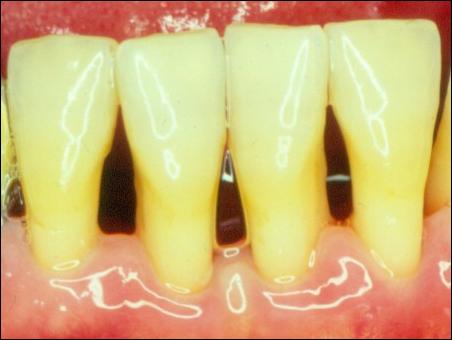

潔完牙后,牙齦組織恢復成粉白色,不再充血發(fā)炎